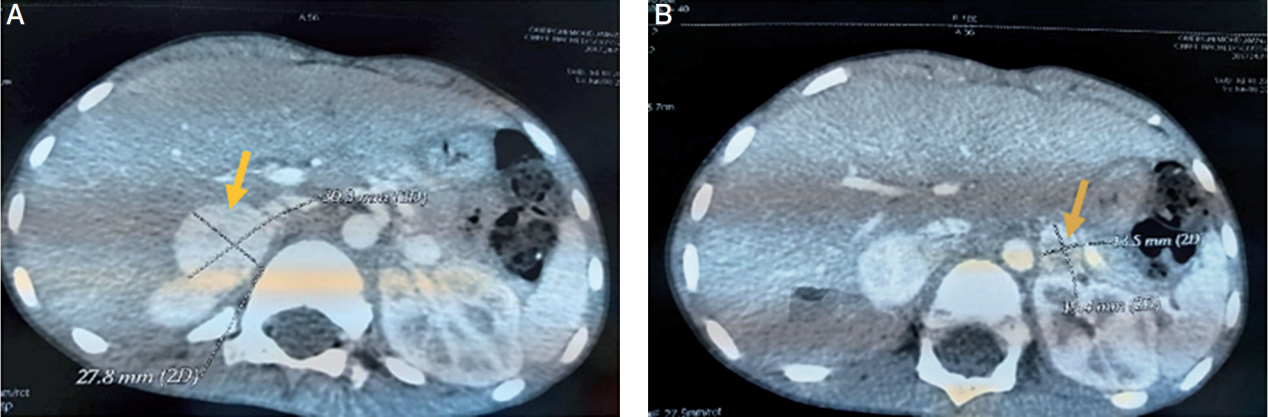

生物学检查显示炎症综合征,CRP为194 mg/l,低血钾血3.4 mmol/l,血糖正常5.5 mmol/l,钠正常135mmol/l,肾功能正常。疑似急性阑尾炎,但腹部超声两次都正常。考虑到持续的腹痛、呕吐和发热,全身状况发生改变,我们通过腹部CT完成了多个双侧肾上腺肿块的检查:右肾上腺边界清楚的2个肿块分别为28*26*31和27*20*25 mm,其他2个肿块分别为10*10*13和17,左侧5*12*16 mm(图1)。临床和放射学表现与嗜铬细胞瘤的诊断一致。

图1